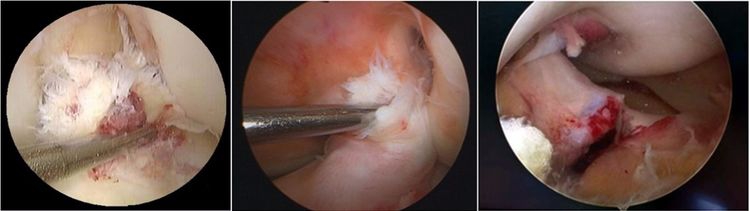

ACL损伤的直接征象:指ACL本身的形态和信号异常。一旦有了明确的直接征象就可以确定ACL损伤。

1.不连续:有韧带的低信号,但中断不连续。一般见于新鲜损伤。

2.方向异常(ACL 下垂征):有较完整的韧带低信号,但方向异常,呈下垂状。一般见于股骨附着部的陈旧损伤,损伤的ACL下垂并粘附在PCL上。

3.ACL 消失:髁间窝空虚,无韧带信号。见于较久的损伤,损伤的ACL撕裂较重呈马尾状,无滑膜包裹,逐渐被关节内的酶腐蚀而消失。

4.撕脱骨折:一般为ACL胫骨附着部的撕脱,韧带完整,信号多正常。

5.假瘤:韧带损伤后断端较整齐,残端组织增生并被滑膜包裹呈"瘤状",如果突出于前方为"独眼征",多见于韧带股骨附着部撕裂及部分撕裂。

6.扭曲和空虚:髁间窝内似隐隐约约有低信号,边缘明显,中央空虚;或者中央有低信号,但扭曲如麻花状。多为陈旧损伤,仅存ACL的滑膜,里面可有少量的韧带纤维,粘附在后方,随着膝关节的长时间屈伸逐渐呈扭曲状。